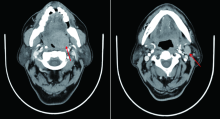

扁桃体黏液表皮样癌是一种罕见的恶性肿瘤,文献中鲜见报道。现报道1例扁桃体黏液表皮样癌患者的诊疗经过,并探讨扁桃体黏液表皮样癌的临床特点、诊断、治疗及预后等。